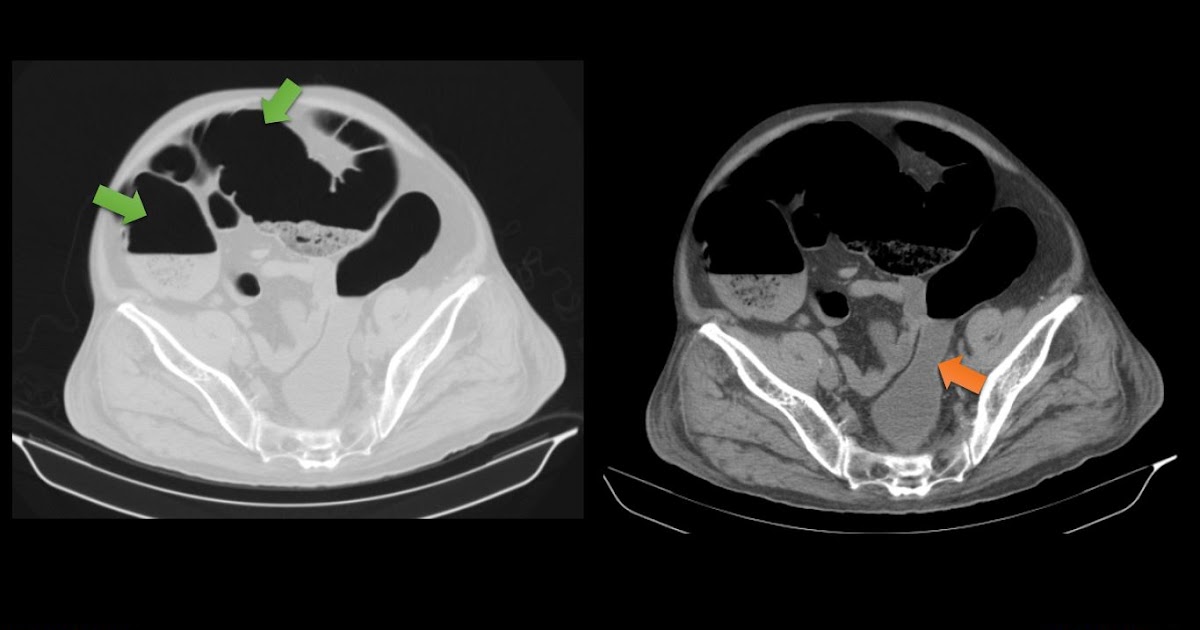

Ogilvie Bowel. In some cases the small bowel.

In some cases the small bowel.

Ogilvie Bowel In some cases the small bowel. In some cases the small bowel.